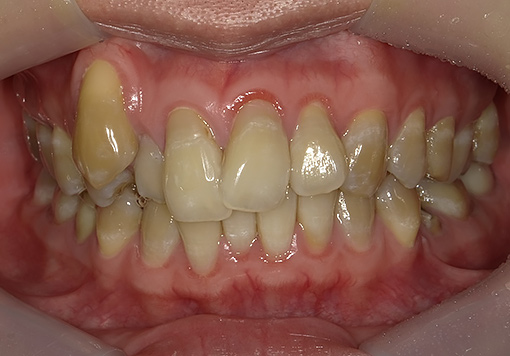

Case 02

before

after

- 主訴:悪いところは治したい

- 治療内容:インプラント、審美補綴、

マウスピース矯正 - 治療期間:40万円

- 診断結果:歯の欠損、歯列不正

- 治療後経過:経過良好

- 治療費用:160万円

リスク・副作用:治療期間が長い、外科的侵襲がある